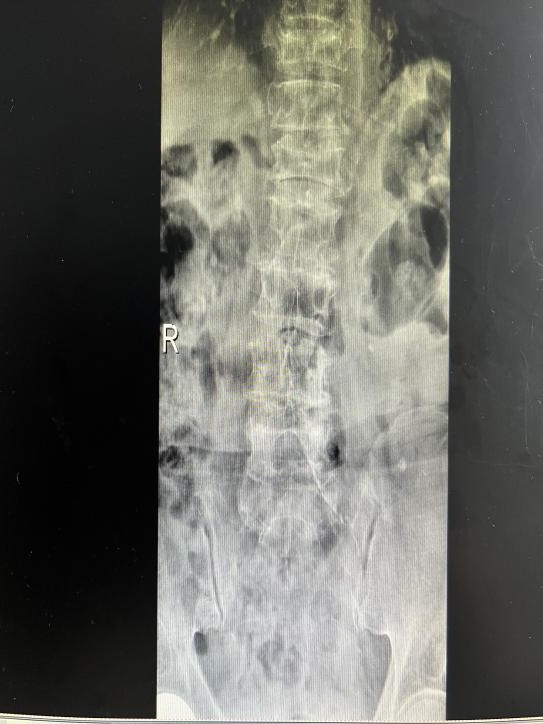

多年来,贵州航天医院各科室紧跟医学前沿,不断强技术、补短板,大力开展新技术、新项目,完成了许多高精尖、高难度、本地区“首例”的技术,填补了医院医疗技术空白,满足了群众日益增长的医疗需求。 贵州航天医院骨科率先在遵义地区开展骨搬移技术,截至目前,已治愈慢性骨髓炎、感染性骨不连、骨缺损、脉管炎、糖尿病足患者200余例,糖尿病足治疗保肢率达到98%。 本期,我们将为大家带来骨科特色技术——骨搬移技术(Ilizarov)。 案例分享 一名59岁的患者,身患糖尿病12年,在来我院3个月前出现了右脚溃烂的症状,来院就诊时,患者的右脚十分红肿,右脚脚趾坏死,伤口处不断流出黑红色脓液,情况十分严重。在接诊到患者时,骨科专家团队高度重视,立刻为患者完善了CT血管造影(CTA)等相关检查,诊断为:2型糖尿病,糖尿病周围血管病变,右糖尿病足。 术 前 考虑到患者情况比较严重,为最大限度保证患者肢体完整,科室专家团队进行了严格的讨论评估,为患者制定了骨搬移技术治疗方案,在征得患者及其家属的同意后,成功通过搬移骨块为患者进行治疗,促进患者病变肢体血管再生。 胫骨横向骨搬移外架固定 清除感染病灶 术后调节外架,通过搬移骨块 促进患肢血管再生 患者在术后三周前来换药,观察到感染得到进一步控制;术后六周复查,患者病变处已愈合,进行CT血管造影(CTA)后可明显观察到足部血管再生。 术后3周 术后6周愈合 CT血管造影见足部血管再生 糖尿病患者全身与局部的问题互为影响,形成恶性循环,糖尿病足溃疡创面迁延不愈,常见干性坏疽、湿性坏疽、趾坏死、深且大的溃疡以及骨髓炎等症状,还可导致脓毒血症,以往为保全生命,患者被迫选择一次或多次截肢。骨搬移技术的发展进步,能在血糖有效控制、局部有效清创下,有效促进患肢微血管再生,改善患肢血供,达到糖尿病足更快治疗康复的目的,并能根据病变情况最大限度的保障患者肢体完整。 什么是骨搬移技术 骨搬移技术是通过使用专用的骨外固定器固定骨段,每天缓慢牵拉,在牵拉搬移过程中,骨段尾部形成新骨及新的软组织,从而修复骨骼缺损及软组织缺损。是治疗大段骨缺损、骨不连、骨感染、肢体畸形的金标准方法,也用于治疗脉管炎、糖尿病足等肢体缺血性疾病。 骨感染缺损 切除感染段 搬移骨段 新骨形成 骨感染根治愈合 骨搬移技术原理 生物组织在持续、稳定、缓慢牵拉下,能刺激细胞分裂、组织再生,骨外固定技术运用该原理,通过持续缓慢调节外固定器形成牵拉张力,促进牵引成骨与相邻组织再生,如神经、血管、肌肉、皮肤等再生,达到治疗大段骨缺损、肢体缺血如糖尿病足等疾病的目的。 骨搬移技术优势 (一)除治疗骨缺损、骨不连外,有更广的适用范围,利用组织再生、血管再生等特性,能大量运用于肢体畸形的矫形、糖尿病足等的治疗。 (二)治疗效果确切,重建肢体外型和功能,极大降低截肢率和残疾率。 (三)明显提高了患者生活质量,极大减轻其家庭及社会负担。 肢体畸形的矫形 慢性骨髓炎 骨段切除 术后1年 濒临截肢的脉管炎术后6周 难愈创面术后3周 贵州航天医院骨科 专家团队 赵学平 骨科主任 主任医师 临床擅长:从事骨科临床工作30余年,对骨科常见疾病的诊治具有丰富的临床经验。 世界中医药联合会脊柱康复专业委员会常务理事,中华中医药学会整脊分会常务委员,中国中西医结合学会骨伤科分会肢体矫形功能重建与康复专家委员会常务委员,中国研究性医院学会骨科创新与转换专业委员会关节外科学组保髋工作委员会常委,中国康复技术转化及发展促进会骨外科与康复技术转化专业委员会常务委员,泛珠三角区域运动医学联盟(PPRD-SMA)理事会常务理事,中国研究型医院学会运动医学专业委员会委员,贵州省中医药学会整脊分会副主任委员,贵州省中西医结合学会银质针专业委员会副主任委员,贵州省康复医学会骨与关节专业委员会常务委员,贵州省人民医院骨科专科联盟常务理事,贵州省康复医学会骨内科专业委员会常务委员,中华医学会贵州省骨科学会委员,贵州省康复医学会脊柱脊髓专业委员会常务委员,贵州省运动医学分会委员,贵州省康复医学会骨与软组织肿瘤专业委员会委员,遵义市医学会创伤分会副主任委员,贵州省康复医学会骨内科专业委员会遵义地区分会常务委员,遵义市医疗事故鉴定、伤残鉴定、工伤鉴定、司法鉴定专家。 长期从事骨科临床研究及教学工作,在国家级、省部级杂志发表论文20余篇,SCI论文2篇,参与主编骨科专著2部,主持省部级科研项目2项,参与指导省部级、市级科研项目6项。 陈明勇 骨科副主任 副主任医师 临床擅长:从事创伤骨科工作约20年,对骨缺损、骨不连、骨肿瘤、肢体畸形等的肢体矫形重建及功能重建,慢性化脓性骨髓炎的根治治疗、糖尿病足的保肢治疗、快速康复理念(ERAS)下的老年骨折的诊治,四肢复杂骨折的诊治,四肢骨折等微创手术治疗具有丰富的临床经验。 2004年毕业于遵义医学院临床专业,曾在中国人民解放军总医院、广西医科大学第一附属医院、上海第六人民医院骨科进修。中国中西医结合学会骨伤科专业委员会横向骨搬移治疗糖尿病足及微血管网再生学组首届委员,遵义市医学会创伤分会常务委员。 瞿 辉 骨科 副主任医师 临床擅长:对骨科的常见病、关节外科、脊柱外科及运动医学疾病的诊治具有丰富的临床经验,熟练掌握骨科手术操作技术。 毕业于遵义医学院临床医学系,2005年前往广州中山大学第一附院骨显微医学部进修学习,2011年前往成都华西医院进修学习,并多次在省内外学习骨科相关知识,是中华医学会骨科分会会员。 赵兴东 骨科 主任医师 临床擅长:擅长骨科的常见病及各种创伤、四肢骨折创伤修复、骨感染、手足疾病的诊治和手足体表畸形的矫形整复,熟练掌握骨科四肢骨病及创伤的手术操作技术,尤其在四肢关节复杂性损伤、手足外伤、组织缺损创面、难治创面的皮瓣修复方面及平足、高弓足矫形方面及四肢慢性疼痛诊治、康复方面具有丰富的临床经验。 硕士研究生,毕业于遵义医学院临床外科系,2015年前往山东省立医院手足外科进修学习;遵义市医学分会创伤分会第一、二届委员,遵义市手外科医学会第二委届员会常务委员;在省级及省级以上期刊发表文章9篇,参编著作2部,参与主持并完成市级课题1项,参与市级课题2项、省级课题1项。 张俊凯 骨科 副主任医师 临床擅长:从事骨科临床工作28年,对创伤骨折、骨感染、骨缺损、骨不连等外科诊治,四肢骨折的微创手术治疗,四肢复杂骨折(如关节内粉碎性骨折、多发骨折等)的损伤控制及手术治疗等具有丰富的临床经验。 1995年毕业于遵义医学院临床专业,2009年前往复旦大学附属医院骨科进修1年。 卢懿明 骨科 副主任医师 临床擅长:从事骨科工作18年,对创伤骨折、四肢骨折的微创手术治疗、四肢复杂骨折(如关节内粉碎性骨折、多发骨折等)的损伤控制及手术治疗,尤其是髋部骨折的PFNA等微创技术,踝关节骨折、膝关节周围骨折的Mipo微创技术等具有丰富的临床经验,开展了4项新技术,发明6项新型专利技术。 2005年毕业于遵义医学院临床专业,2017年,前往南方医科大学第三附属医院骨科进修半年,回院后运用Mipo技术对骨干骨折及干骺端骨折的治疗技术,同时积极开展骨盆骨折、髋臼骨折腹直肌外侧切口的应用;发表了多篇专业论文,经常参与省内外学术交流会授课,获得医院荣誉称号多个。 邬夏荣 骨科 副主任医师 临床擅长:从事骨科工作16年,对四肢复杂骨折、骨肿瘤的诊治,尤其是足踝创伤、慢性踝关节损伤、平足症等诊疗具有丰富的临床经验。 2006年毕业于遵义医科大学临床医学专业,曾在陆军军医大学西南医院进修学习,发表多篇骨科学术论文。 余德怀 骨科 副主任医师 临床擅长:从事骨科工作10余年,对运动医学、骨关节、脊柱外科常见病、多发病的诊治具有丰富的临床经验。 硕士研究生,2011年毕业于遵义医学院临床医学专业,曾前往遵义医科大学附属医院运动医学专业进修学习;是贵州省医学会运动医学分会青年委员,西部关节镜联盟委员;发表多篇骨科学术论文。 冯 乾 骨科 副主任医师 临床擅长:从事骨科工作近20年,熟练掌握骨科多发病及常见病的诊治,尤其对脊柱退变性疾病的诊断及治疗具有丰富的临床经验,主要研究脊柱微创相关治疗方式,能熟练开展椎间孔镜及VBE。 曾前往北京大学第三医院进修学习疼痛及椎间孔镜、首都医科大学友谊医院专业进修脊柱内镜;是贵州省康复医学会第三届脊柱脊髓专业委员会委员;发明专利3项、发表脊柱外科专业论文多篇。 张艳金 骨科 副主任医师 临床擅长:从事骨外科工作16年,对复合伤、多发伤的救治、四肢骨干骨折、关节周围骨折、骨肿瘤、骨髓炎等诊治具有丰富的临床经验。 中共党员,硕士研究生,2006年本科毕业于山西医科大学第二临床医学院,2011年研究生毕业于北京军区总医院;在“老年COPD患者合并髋部骨折的诊治”国际合作课题组研究两年,在老年髋部骨折的诊治方面具有丰富的经验,并发表论文6篇;承担遵义市级课题1项;承担遵义医科大学的临床教学工作,获得遵义医科大学优秀带教老师荣誉。编撰有《骨科疾病诊疗精粹》一书,开展2项新技术,编撰地方规范《务川自治县创伤骨科常见疾病诊疗规范》一书。 赵小锋 骨科 副主任医师 临床擅长:从事骨科临床工作11年,对骨科常见病、多发病诊疗有较为丰富的临床经验,擅长脊柱相关疾病诊断及治疗,尤其是颈、腰、腿疼痛疾病诊断及治疗,擅长胸腰椎骨折微创经皮穿刺内固定术、经皮穿刺椎体成形术、经皮穿刺脊柱内镜下腰椎间盘摘除术、单纯开创腰椎间盘摘除术、腰椎滑脱复位椎间植骨椎融合内固定术、腰椎管狭窄减压融合内固定术及人工髋、膝关节置换术等。 2012年毕业于遵义医学院外科学专业硕士研究生,2019年参加“遵义市115医学人才精英计划”于上海交通大学第一附属医院培训学习,2023年于北京大学第三人民医院脊柱外科进修学习,曾获得遵义市优秀医师荣誉称号。 遵义市手外科第一届委员,遵义市医学会创伤分会第一届委员,遵义市医学会创伤分会第二届委员,贵州省康复医学会第三届脊柱脊髓专业会委员,遵义市医学会烧伤与整形外科学分会委员,发表论文5篇,其中国家级核心期刊1篇,SCI论文1篇,主持市级课题1项并结题,参与市级课题2项。 贵州航天医院骨科简介 基本情况 贵州航天医院(原3417医院)骨科组建于1968年,前身是以创伤和断肢(断指)再植闻名于世的上海市第六人民医院骨科,中国断肢(断指)再植的奠基者、中科院院士陈仲伟等著名专家、学者多次莅临科室指导医疗、教,是贵州省最早拥有专业骨科技术科室之一,在70年代开展了贵州省首例断肢(断指)再植手术。组建50余年来,诊治患者已逾百万,挽救了无数的伤病员,成为了保障遵义地区人民群众健康的重要支撑。 经过几代人的不懈努力,今天的骨科,已由创伤骨科发展至骨病、骨肿瘤、骨结核等领域,现有脊柱外科、关节外科、四肢创伤、手足外科四个亚专科,成为了集医疗、教学、科研于一体的综合学科,是贵州省临床重点专科、遵义市临床重点专科、遵义市骨科临床医学中心、遵义市基层骨科专科联盟理事长单位。 科室目前开放床位110张,共有医护人员50余人,副高级以上专家18人,硕士研究生15人。拥有一流骨科医疗设备多台,每年不定期选派优秀技术骨干到全国各大知名医学院校进修、学习、参观、交流,并邀请国内、国外知名专家教授来院进行交流、指导,通过不断引进国内外先进的诊疗技术,科室医疗技术水平稳步提升,为广大人民群众提供了优质的医疗服务。 专科特色 骨一科 (一)骨缺损、骨不连的肢体与功能重建 胫骨横向骨搬移技术治疗糖尿病足: (二)慢性骨髓炎的根治治疗 (三)肢体缺血性疾病如糖尿病足、脉管炎的保肢治疗 (四)皮瓣修复 (五)复杂创伤的治疗 (六)老年髋部骨折及小儿骨折快速手术 老年髋部骨折: 骨二科 (一)胸腰椎骨折微创经皮椎弓根螺钉固定术 (二)老年性骨质疏松性患者腰椎滑脱脊柱内固定术(骨水泥螺钉) (三)V形双通道脊柱内镜技术(VBE)腰椎融合术治疗腰椎退行性疾病 (四)老年性骨质疏松性骨折(PVP/PKP)术 (五)人工髋关节置换术 (六)双侧股骨头坏死人工全髋关节置换 (七)右侧全髋置换术后假体周围骨折翻修 (八)人工膝关节置换术 (九)人工膝关节假体松动翻修 (十)关节镜技术 传统手术切口 关节镜技术切口 诊疗范围 骨一科 1.四肢创伤、矫形。 2.手、足踝外科。 骨二科